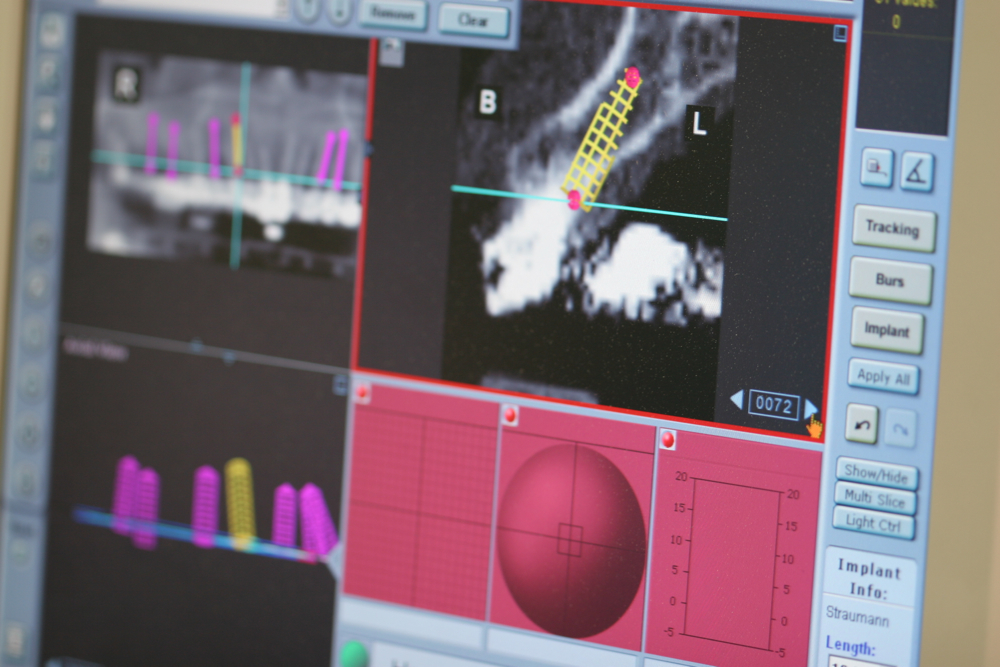

The management of complex dental rehabilitation requires careful planning and consideration of all the associated problems. When managing complex cases, it is usually necessary for other specialist clinicians to be involved in restoring the mouth to normal. This provides the best chance to correct any underlying problems that caused tooth destruction, and may reduce the amount of prosthetic work you require. We frequently work alongside other specialists such as Orthodontists, Periodontists, Endodontists and Maxillo-facial Surgeons to develop solutions to your individual problems.

Dr Parzham has an interest in the management of complex multi-disciplinary rehabilitations of severely broken down teeth.